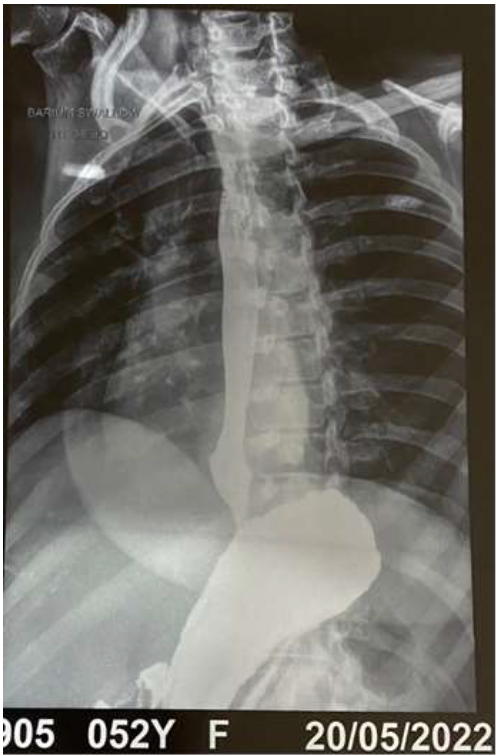

With a valid consent Endoscopic PEG tube placement was done. Through the PEG tube, Freka nasojejunal tube was placed into duodenum-literally PEG-D. Then the fistula rent was closed using 10 Large Haemostatic Clips. The mucosal defect appeared approximated. The patient improved over next few days, ICD’s were removed, extubated from ventilator support and oxygen requirement came down and slowly was shifted back to rehabilitation on PEG feeds and on antibiotics. Six weeks later, small beak like contained leak was noted in distal third portion on Gastrograffin swallow. She was continued on PEG feeds and on follow up at the end of 3 months, contrast swallow showed no leak and there was a pseudodiverticulum appearance on check Endoscopy. She was then initiated on oral feeds and PEG tube was removed. She did well on subsequent follow up a month later.

Figure-4: Contrast swallow- no leak